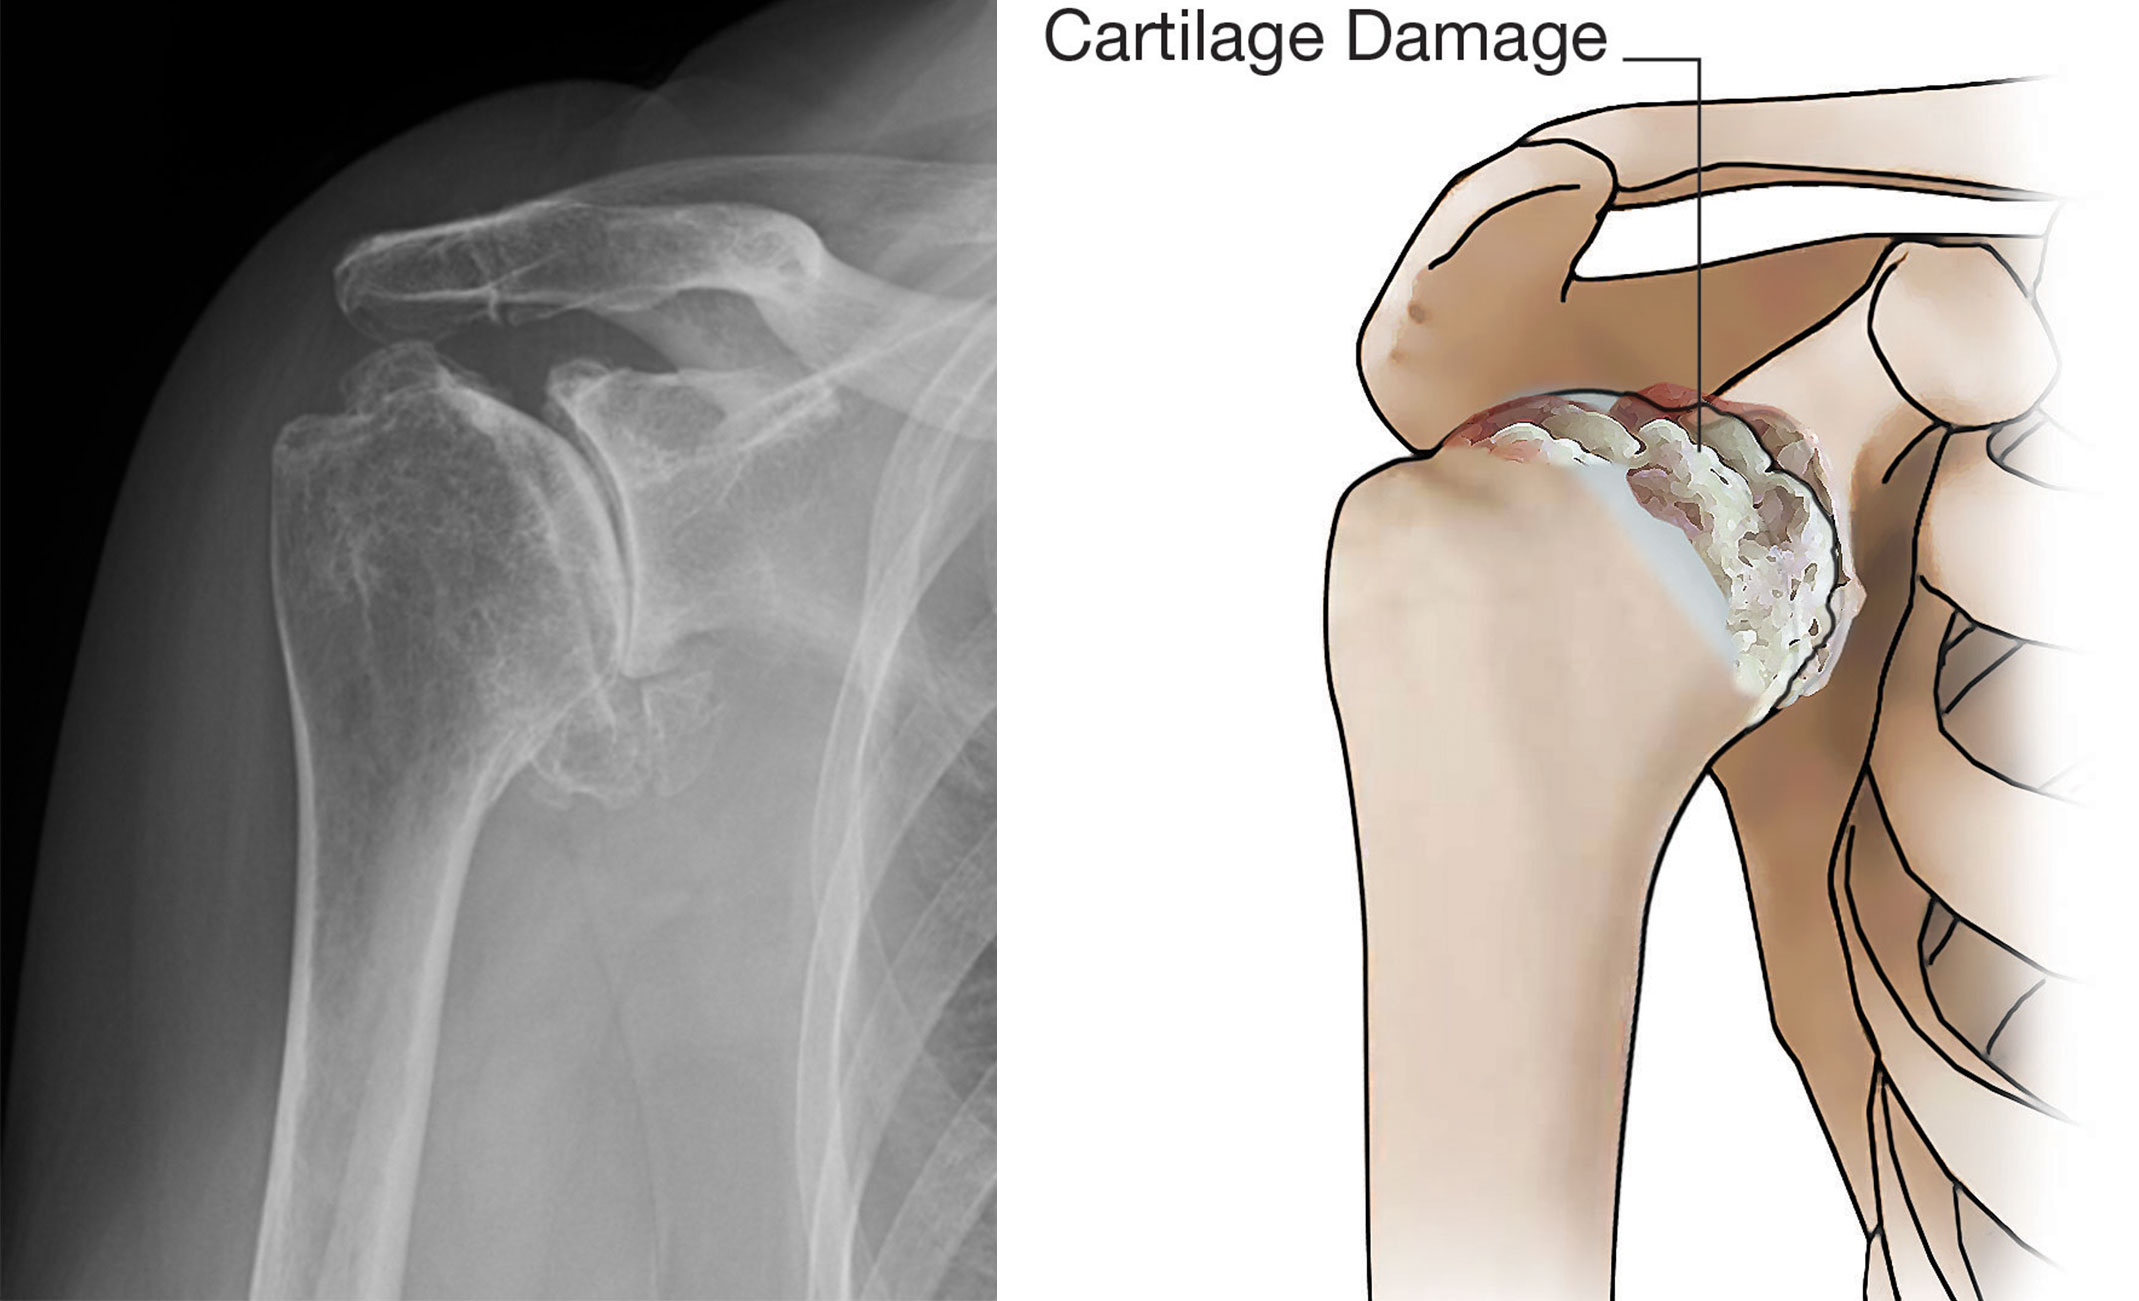

X-ray and illustration showing osteoarthritis of the shoulder

An X-ray and illustration showing damaged cartilage in the glenohumeral joint.

Illustration reproduced and modified with permission from JF Sarwark, ed: Essentials of Musculoskeletal Care, ed 4. Rosemont, IL, American Academy of Orthopaedic Surgeons, 2010.

Osteoarthritis

Also known as "wear-and-tear" arthritis, osteoarthritis is a condition that destroys the smooth outer covering (articular cartilage) of bone. As the articular cartilage wears away, it becomes frayed and rough, and the protective space between the bones decreases. During movement, the bones of the joint rub against each other,  causing pain; this is often referred to as "bone on bone" arthritis.

Osteoarthritis usually affects people over the age of 50 and is more common in the acromioclavicular joint than in the glenohumeral shoulder joint.